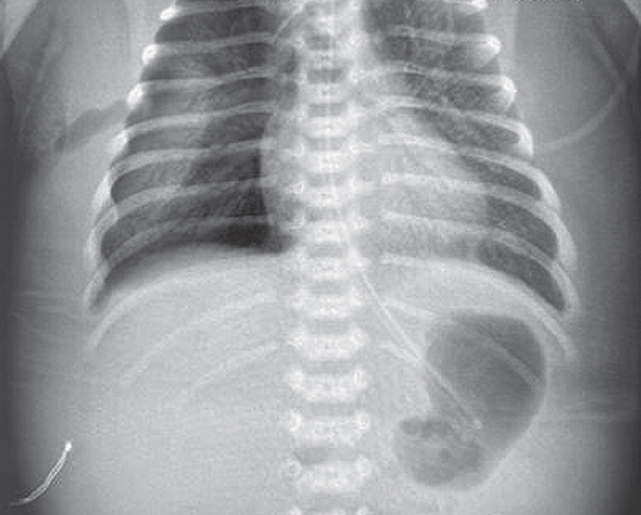

Состояние ребенка с рождения средней степени тяжести, обусловленное явлениями респираторного дистресса (умеренное втяжение межреберий, стонущее дыхание, тахипноэ до 60 в минуту), что потребовало проведения неинвазивной искусственной вентиляции легких (ИВЛ, nСРАР — nasal continuous positive airway pressure) c первых минут жизни [2]. На рентгенограмме отмечаются признаки транзиторного тахипноэ новорожденного (рис. 1).

Рис. 1. Рентгенограмма органов грудной клетки новорожденного с клиническими признаками респираторного дистресс-синдрома через 2 ч после рождения

Fig. 1. Chest X-ray of newborn with clinical signs of respiratory distress 2 hours after birth